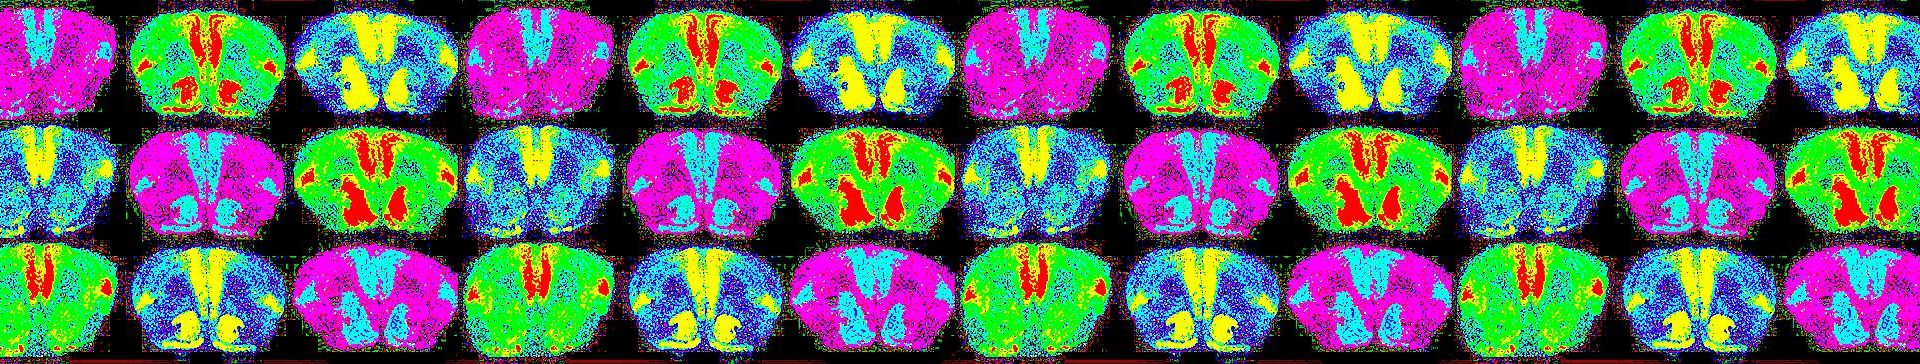

Много е трудно да се контролира усещането за романтична любов и това е защото тя е основен нагон. Тя е допаминова мозъчна пътека, невронна верига, която е далеч под кората на главния мозък, в който се случва мисленето, далеч под лимбичната система, където се организират емоциите. Тази верига е в самата основа на мозъка и всъщност основната мозъчна актичност, която откриваме, е в част на мозъка, която е в непосредствена близст до тези части, които отговарят за усещането на глад и жажда. Романтичната любов на практика е нагон, основен нагон за оцеляване и репродуциране. Еволюирал е милиони години, за да фокусира репродуктивната ви енергия върху един партньор, за да започне процесът на репродуцирзане.

Да. Имахме възможност да изледваме 100 човека със скенер. Първата група бяха 70 души, които в момента са влюбени. Втората група – 15 човека, които са били отхвърлени и третата група бяха хора, които са в дългогодишна връзка, но все още са влюбени в партньорите си.

При хората, които са били отхвърлени, открихме активност в част в мозъка, която се активира при зависими хора в абстиненция. Същият регион в мозъка, който реагира при зависимост към хероин, кокаин, алкохол, никотин, храна или комар, става активен, когато сме влюбени. Написах огромен академичен труд, в който накрая казвам, че може би трябва да преразгледаме разбирането си за това, що е то пристрастяване. Много хора смятат, че пристрастеността е изцяло патологична и това е така.

Но също така смятам, че романтичната любов е естествено пристрастяване – когато нещата вървят добре и сте влюбени в правилния човек, е всъщност много положително пристрастяване, не патологично. Разбира се, би могло да бъде и много лошо пристрастявене – когато сме отхвърлени, в мозъка се активират региони, които са активни и при физическа болка, тревогата свързана с нея, региони свързани със силен копнеж и тези, свързани с пристрастяване. Така че, романтичната любов е пристрастяване сама по себе си, което е започнало еволюцията си преди милиони години и, ако оцелеем като вид, ще бъде с нас милиони години напред.